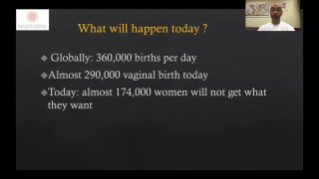

Supportata dalla piattaforma avanzata ZST+, la gamma completa di soluzioni smart di Nuewa ├© progettata appositamente per migliorare la salute della donna durante il periodo pre-gravidanza, la gravidanza e il recupero post-parto, per fornire diagnosi complete ed efficaci e per rispondere a sfide cliniche sempre pi├╣ impegnative.